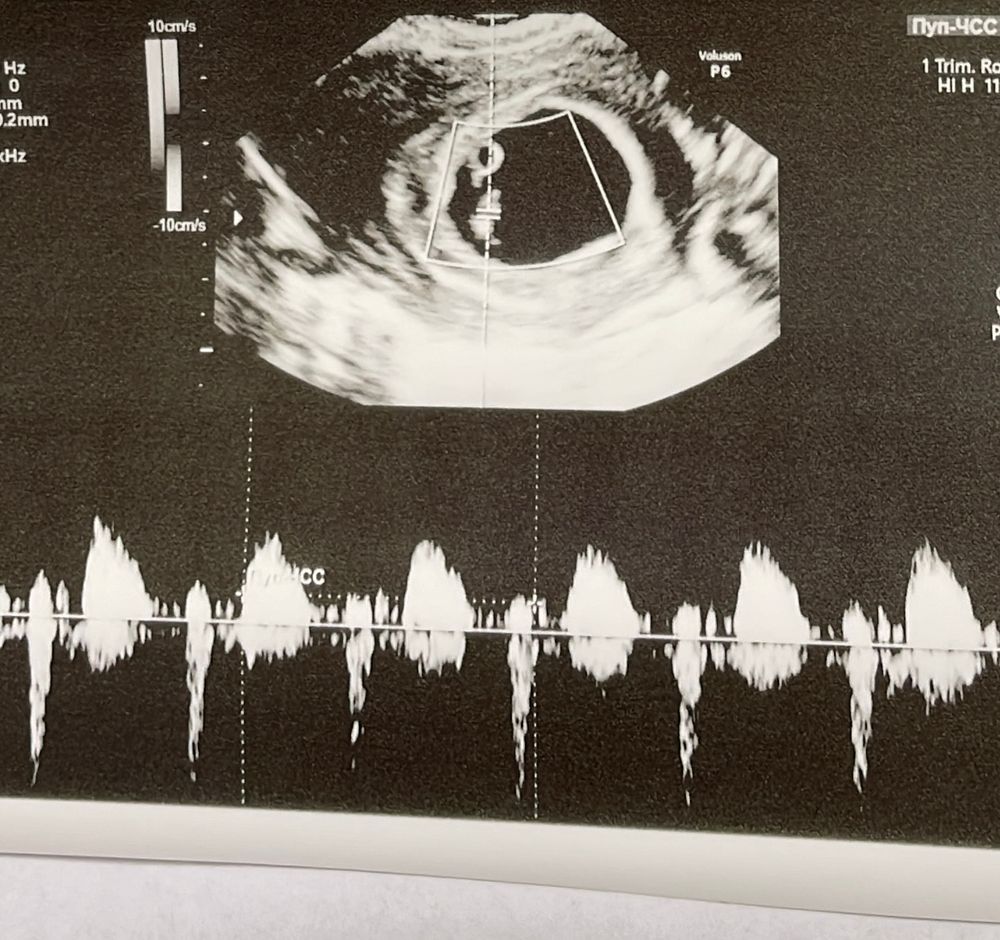

Контрольное УЗИ на 31дпп

И так сегодня 6 недель и 3 дня. 11.11 была подсадка 1 пятидневочки. Сегодня услышали чсс 149. ЖМ 3.2. Эмбрион 8. ПЯ 26. Вообщем все отлично! Био родители счастливы🙏🏼